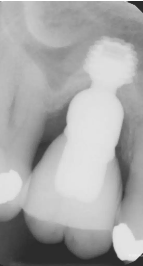

Caso Bicon: Seguimiento radiográfico de siete años de un implante Bicon SHORT® de 6,0 x 5,0 mm con un pilar de elevación de seno y una corona de pilar integrada (IAC)

Seguimiento radiográfico de siete años de un implante Bicon SHORT® de 6,0 x 5,0 mm con un pilar de elevación de seno y una corona de pilar integrada (IAC)

Presentamos el caso de un paciente masculino de 69 años, en el que se realizó la extracción dental seguida de la colocación de un implante Bicon SHORT® de 6,0 x 5,0 mm con pilar de elevación de seno.

El caso se restauró con una corona de pilar integrado (IAC) de 20 mm de longitud y ha sido seguido durante 84 meses.

Este caso destaca no solo por la estabilidad a largo plazo del implante corto, sino también por mostrar de forma radiográfica la aplicación de la Ley de Wolff: el hueso se adapta y se refuerza en respuesta a la carga funcional.